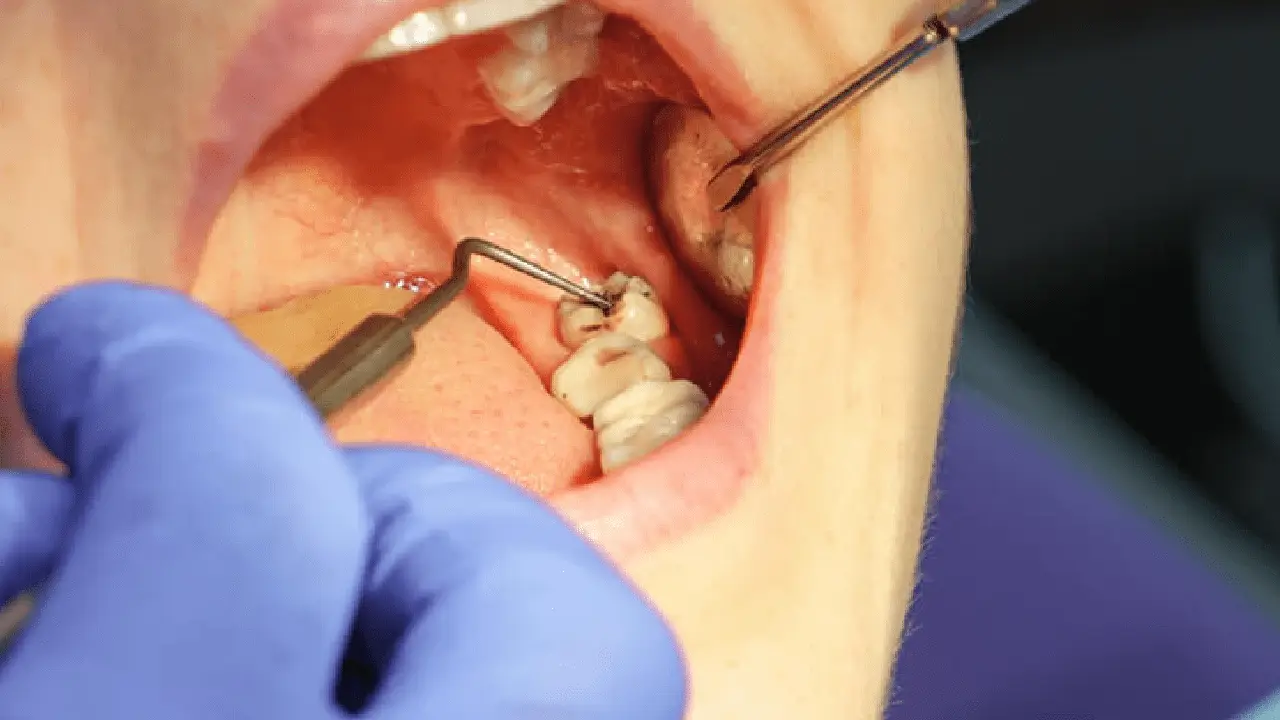

Traditional Wisdom Tooth Extraction

This method involves using forceps and an elevator to extract the wisdom tooth. The dentist may need to incise the gum, widen the socket, and apply force to loosen and remove the tooth. While this approach is cost-effective and accessible, it can lead to more pain, swelling, bleeding, and a longer recovery time compared to modern techniques like Piezotome, which offer a gentler and less invasive experience.